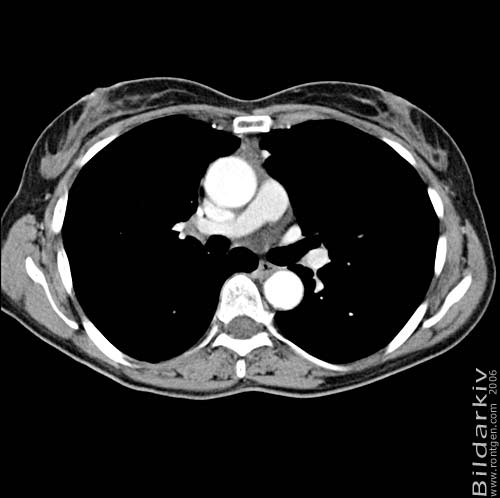

Thorax 28

Snitt över thorax med kontrast. Sk. mediastinum-fönstersättning.

CT Röntgen Helsingborgs lasarett

Mediastinum